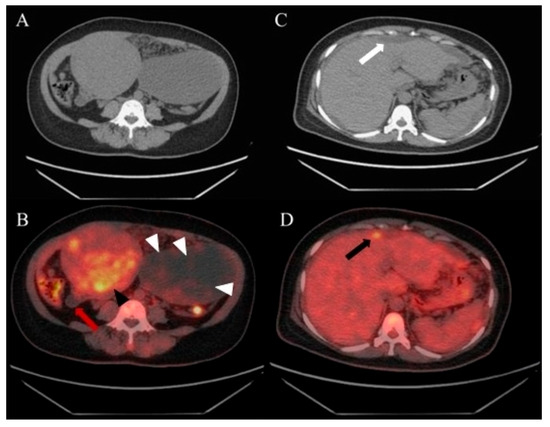

Figure 1. A 50-year-old woman complaining of pelvic heaviness for months and abdominal ultrasounds revealed a mixed-echogenic uterine mass and a cystic lesion with hyperechoic septa. Serum CA-199, CEA, and CA-125 level were elevated. Exploratory laparoscopy and biopsy confirmed a fundal myoma, left ovarian cyst, and mucinous material disseminated throughout the peritoneal and pelvic cavities, with deposits found involving ovaries, spleen, liver, and the peritoneal surface of the diaphragm. Omental biopsy indicated pseudomyxoma peritonei (PMP), suspected origins from the appendix or ovaries. To evaluate the systemic involvement, the 18F-FDG PET/CT was performed and displayed, no apparent supra-diaphragmatic FDG uptake, a uterine mass with moderate FDG uptake ((A), unenhanced CT image; (B), indicated by a black arrowhead), consistent with a diagnosis of uterine myoma, poorly FDG-avid, strand-like appearance within the left ovarian cystic lesion ((B), white arrowheads), physiologic FDG uptake in the compressed descending colon posterior to the cystic ovarian lesion (B), and a cystic appendix showing no FDG uptake ((B), red arrow). Note the CT showed scalloping of the liver surface ((C), white arrow) accompanied by an uneven FDG-avid extrahepatic lesion ((D), black arrow). Several FDG-avid areas were also observed on the omentum.